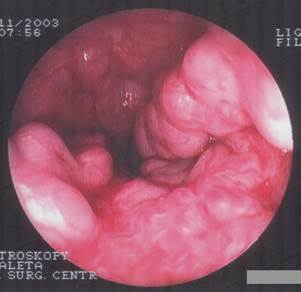

Эзофагогастродуоденоскопия (ЭГДС)

Метод позволяет выявить и характеризовать варикозные вены в пищеводе и кардиальном отделе желудка. К данному исследованию у больных СПГ следует подходить с особой осторожностью. Травма истонченных варикозных вен может вызвать тяжелое пищеводное кровотечение. С другой стороны, выполнение исследования в экстренном порядке может быть затруднено вследствие продолжающегося кровотечения.

При осмотре ВРВП выявляются как расширенные и извитые стволы подслизистого слоя (рис. 2). Различают изолированные варикозные узлы и расширенные стволы и сплетения. По степени выраженности различают одиночные венозные стволы; венозные сплетения в области кардии и венозные сплетения, переходящие на пищевод. Цвет варикозных вен зависит от глубины залегания. При поверхностном – вены имеют голубую окраску и выбухают в просвет как тяжи или узлы. При глубоком залегании, на фоне розовой оболочки пищевода видны продольные извитые тяжи того же цвета. Они не спадаются при раздувании пищевода воздухом или надавливании на них эндоскопом. Одновременно оцениваются пептические изменения слизистой пищевода, что позволяет прогнозировать вероятность кровотечения. Следует отметить, что у больных СПГ часто наблюдаются воспалительные и эрозивные изменения слизистой пищевода вследствие гастроэзофагеального рефлюкса.

Рис. 2. ФЭГДС. Варикознорасширенные вены пищевода.

В нашей клинике разработан протокол комплексной оценки состояния вен пищевода и желудка, согласно которым выделяют четыре степени ВРВП. В основу протокола положены принципы регистрации эндоскопических признаков ВРВП, предложенные Японским обществом по изучению портальной гипертензии в 1991 году. При выполнении исследования определяется локализация, протяженность и форма вен пищевода и желудка, а также наличие так называемых «вишневых пятен» и «красных знаков», которые являются предвестниками кровотечения. Обнаруженные изменения отмечают в виде стандартной схемы, которая позволяет врачу-эндоскописту четко представить себе имевшуюся ранее у больного патологию (Э.М. Колесников, В.В. Троян 2004).

Протокол эндоскопического исследования позволяет достаточно подробно и объективно оценить степень варикозного расширения вен, позволяет проводить динамическую оценку эффективности ЭС и прогнозировать риск развития кровотечений в будущем. Не менее важным является тот факт, что таким образом обеспечивается преемственность у больных с СПГ, которые могут годами лечиться в разных учреждениях и у разных врачей.

Таким образом, ультразвуковые методы обследования позволяют оценить состояние сосудов печени и селезенки, характер и скорость кровотока в ВВ, наличие и характер коллатералей. Спленопортография показывает точную локализацию блока, анатомическую архитектонику сосудов, диаметр селезеночной и воротной вен, наличие коллатералей и путей окольного кровообращения. Рентгенологическое исследование помогает выявить гастро-эзофагеальный рефлюкс и варикозные вены в пищеводе, оценить состояние его функции. Протокол эндоскопического обследования всесторонне характеризует варикозно расширенные вены пищевода и состояние слизистой оболочки. Указанные методы исследования позволяют определить наиболее рациональную тактику лечения и оптимальный метод хирургического вмешательства для каждого больного.